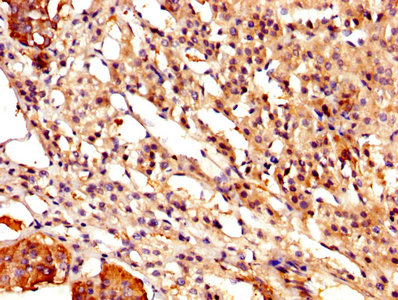

IHC image of CSB-PA004561YA01HU diluted at 1:500 and staining in paraffin-embedded human lymph node tissue performed on a Leica BondTM system. After dewaxing and hydration, antigen retrieval was mediated by high pressure in a citrate buffer (pH 6.0). Section was blocked with 10% normal goat serum 30min at RT. Then primary antibody (1% BSA) was incubated at 4°C overnight. The primary is detected by a biotinylated secondary antibody and visualized using an HRP conjugated SP system.

IHC image of CSB-PA004561YA01HU diluted at 1:500 and staining in paraffin-embedded human adrenal gland tissue performed on a Leica BondTM system. After dewaxing and hydration, antigen retrieval was mediated by high pressure in a citrate buffer (pH 6.0). Section was blocked with 10% normal goat serum 30min at RT. Then primary antibody (1% BSA) was incubated at 4°C overnight. The primary is detected by a biotinylated secondary antibody and visualized using an HRP conjugated SP system.